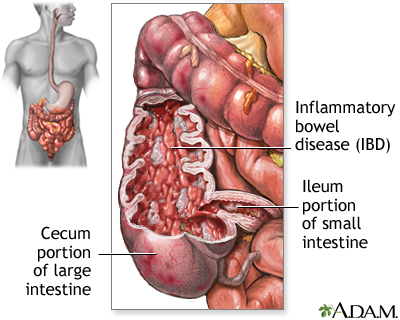

Crohn Disease

Crohn disease, an inflammatory bowel disorder, leads to poor reabsorption of bile salts from the digestive tract and substantially increases the risk for gallbladder disease. Patients over age 60 and those who have had numerous bowel operations (particularly in the region where the small and large bowel meet) are at especially high risk.

Acute appendicitis, inflammatory bowel disease (Crohn disease or ulcerative colitis), pneumonia, stomach ulcers, gastroesophageal reflux and hiatal hernia, viral hepatitis, kidney stones, urinary tract infections, diverticulosis or diverticulitis, pregnancy complications, and even a heart attack can potentially mimic a gallbladder attack.